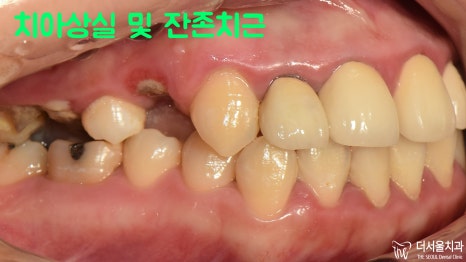

『초진』

툭 튀어나온듯한 입매와 다수의 치아 상실,

이 두 가지 문제가 관찰되었습니다.

이외에도 벌어진 앞니를 비롯하여

여기저기 상태가 좋지 않은 치아들이

구강 곳곳에 자리를 잡고 있었는데요.

앞니를 비롯하여 치료를 받았던 치아들이

꽤 많이 있는 것을 알 수 있었습니다.

오래전부터 치열이 마음에 들지 않으셨고

관리를 소홀히 하여 상태가 좋지 않음을

이미 알고 계셨던 분이었는데요.

비용과 시간, 여러 면에서 치료를 망설이다가

더 늦기 전에 진료를 받아야겠다는 생각에

저희 더서울을 내원해 주셨던 분입니다.